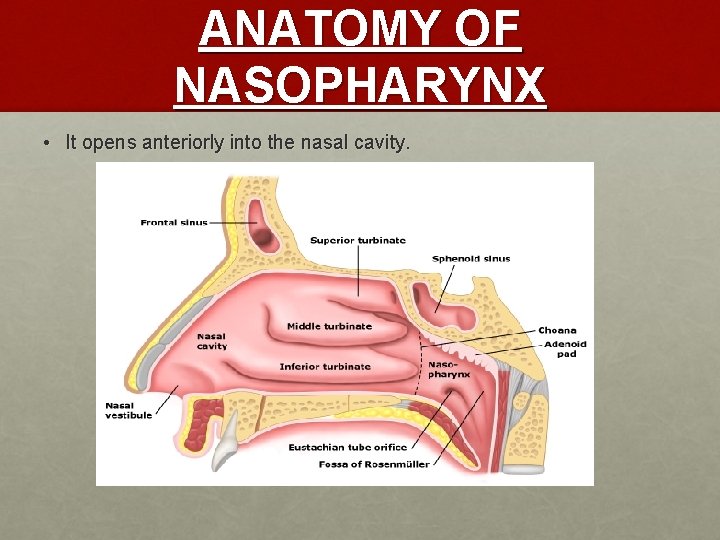

ANATOMY OF NASOPHARYNX • It opens anteriorly into the nasal cavity.